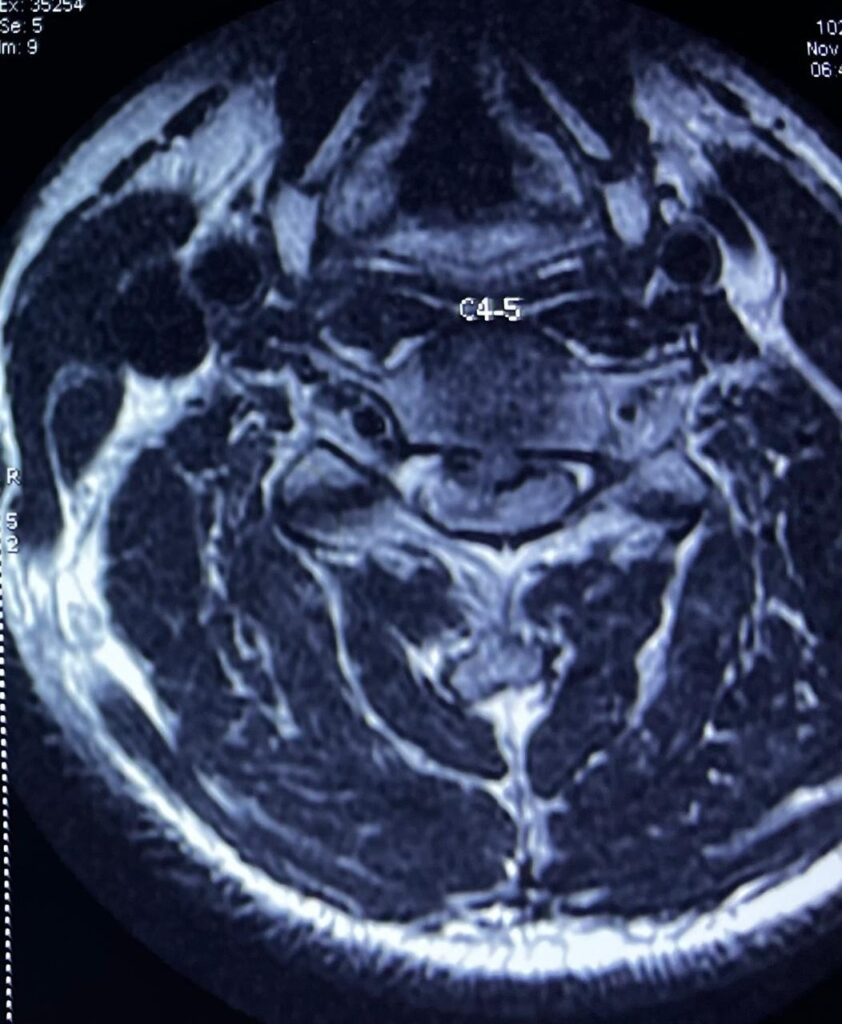

The scan showed disc prolapse at the C4-5 and C5-6 levels, with severe compression of the spinal cord. The paralysis of his right hand and leg was due to this compression. A diagnosis of cervical myelopathy was made , and as the patient was rapidly deteriorating, surgery was advised. The patient was taken up for surgery after a detailed discussion with his family regarding the risks, benefits, and possible outcomes. Surgery (Anterior Cervical Discectomy and Fusion (ACDF)) was done at the C4-5 and C5-6 levels.

The surgery involved approaching the spine from the front (anterior), removing the discs at C4-5 & C5-6 (discectomy), thereby relieving the pressure on the spinal cord, and placing a bone graft in the empty disc spaces (fusion) and fixing them with a titanium plate and screws.